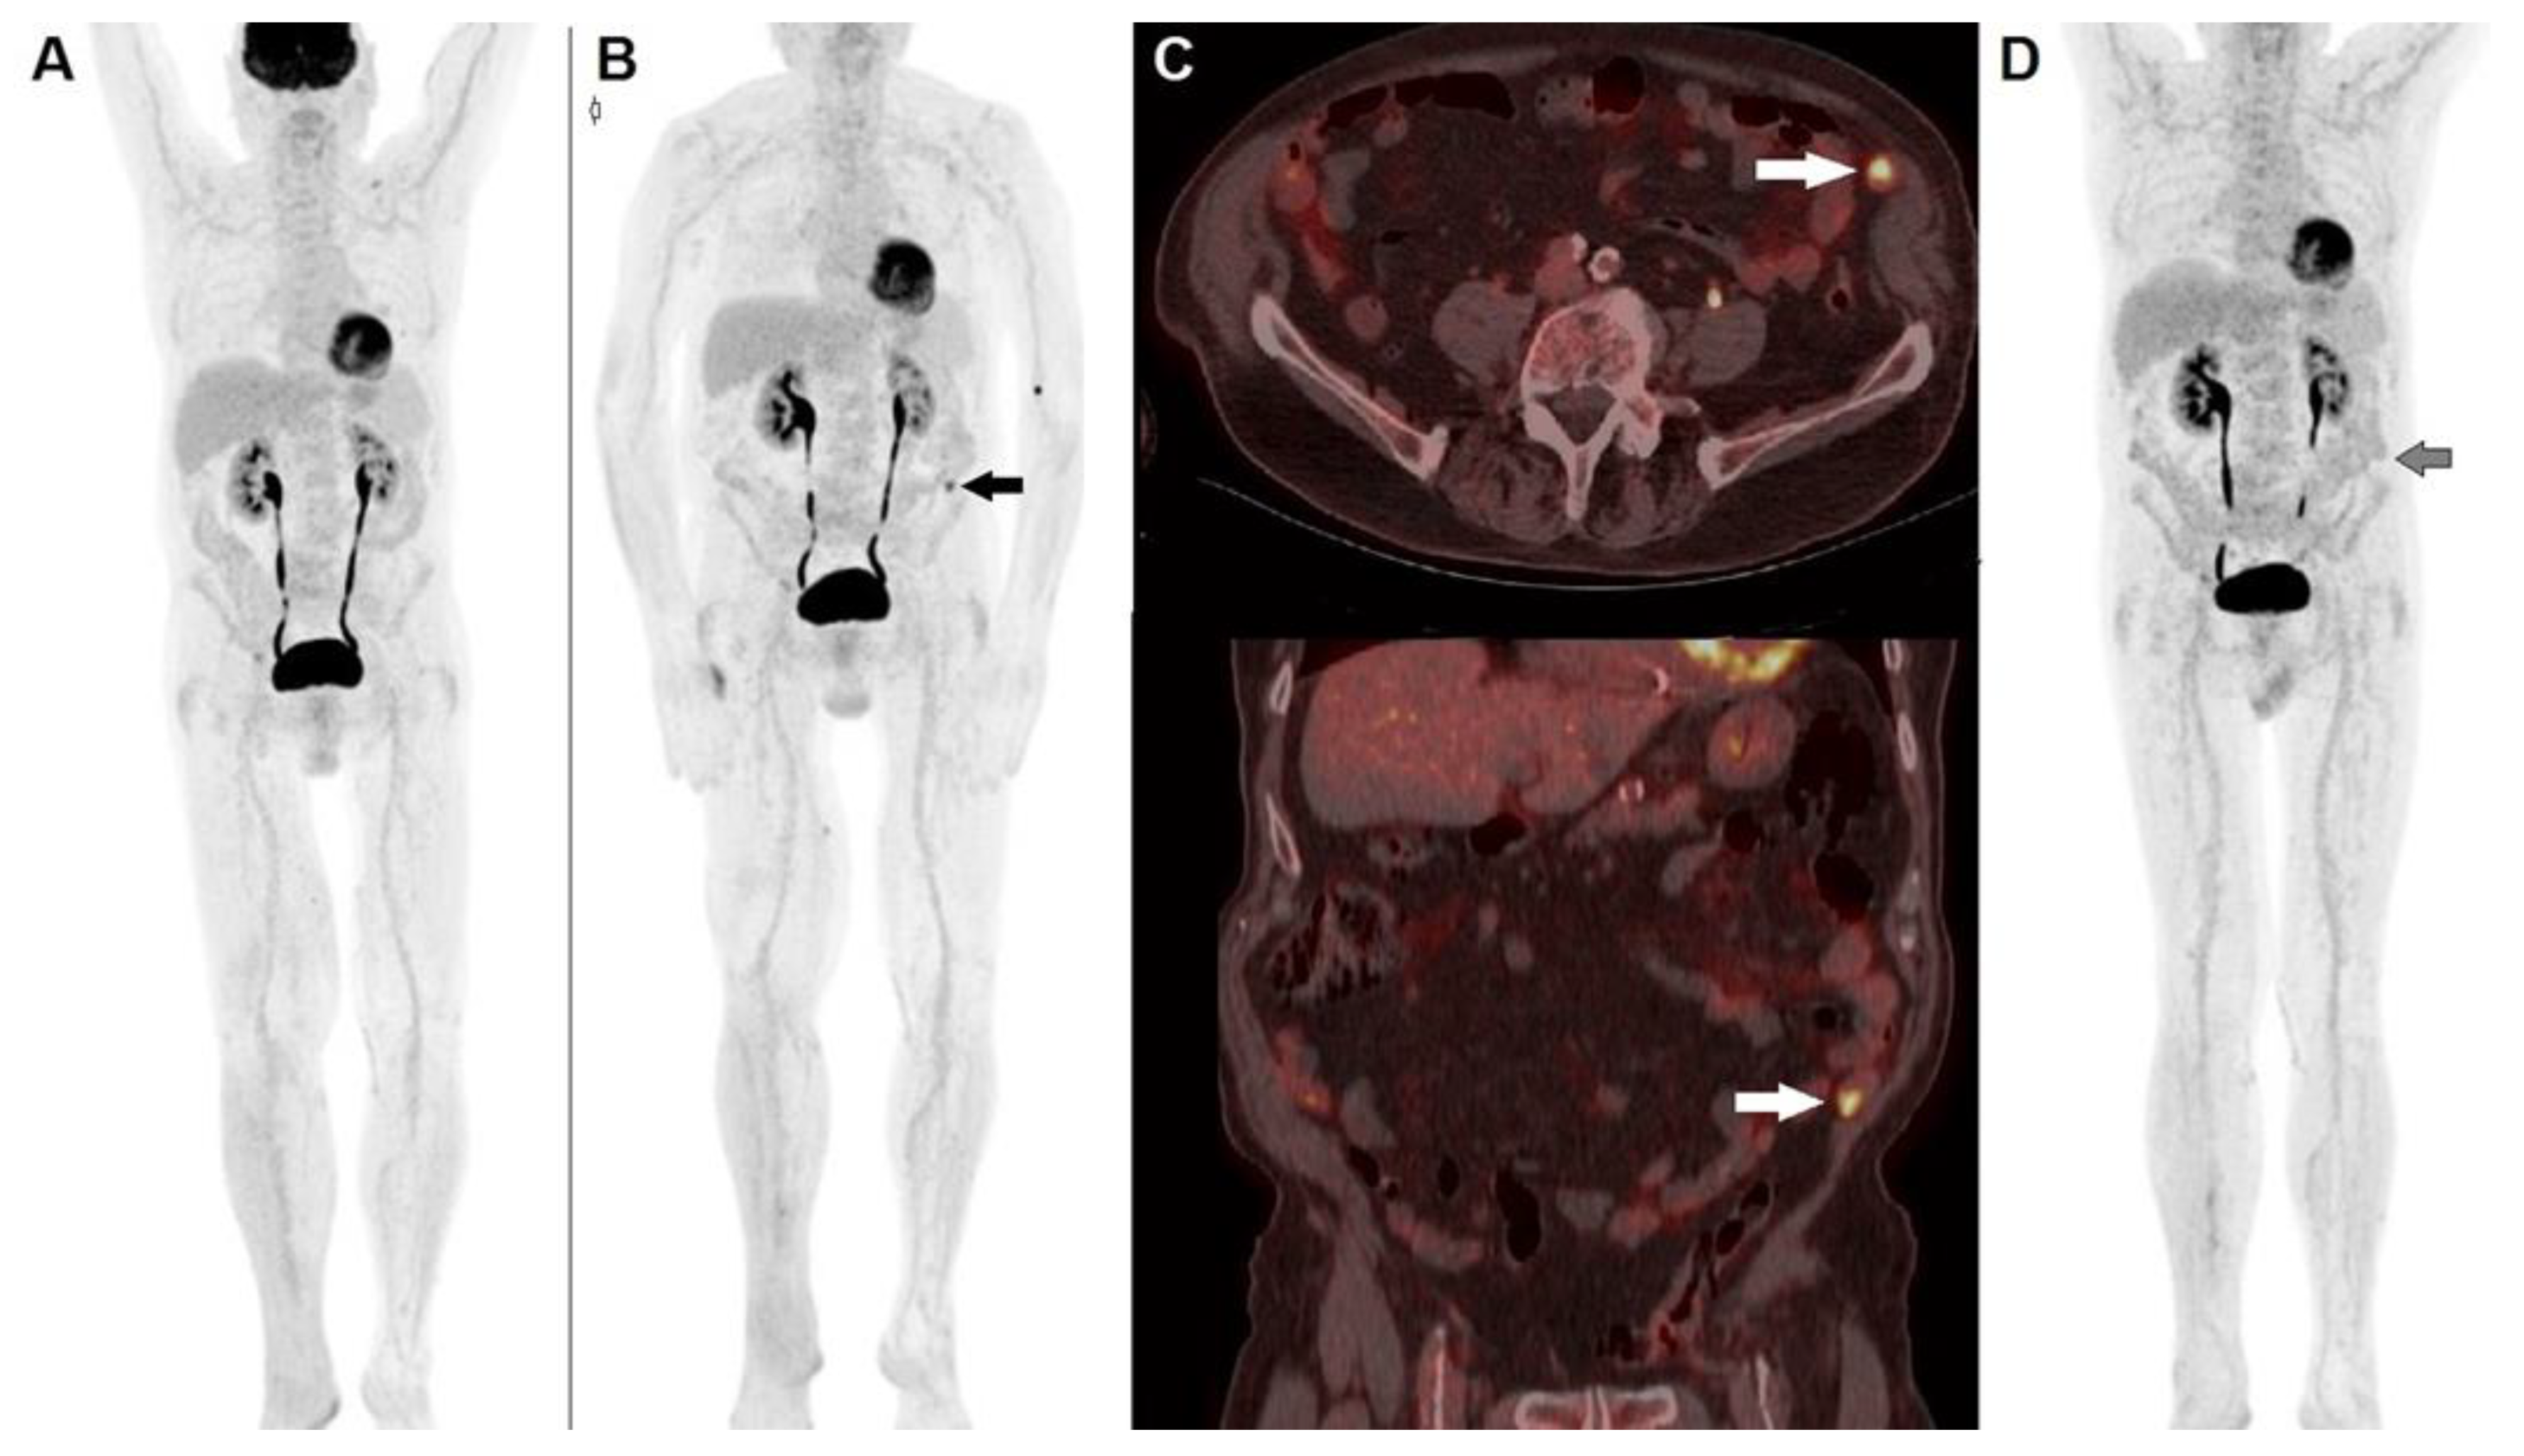

- Anwar, H.; Sachpekidis, C.; Winkler, J.; Kopp-Schneider, A.; Haberkorn, U.; Hassel, J.C.; Dimitrakopoulou-Strauss, A. Absolute Number of New Lesions on 18F-FDG PET/CT Is More Predictive of Clinical Response than SUV Changes in Metastatic Melanoma Patients Receiving Ipilimumab. Eur. J. Nucl Med. Mol. Imaging 2018, 45, 376–383. [Google Scholar] [CrossRef]

- Goldfarb, L.; Duchemann, B.; Chouahnia, K.; Zelek, L.; Soussan, M. Monitoring Anti-PD-1-Based Immunotherapy in Non-Small Cell Lung Cancer with FDG PET: Introduction of IPERCIST. EJNMMI Res. 2019, 9, 8. [Google Scholar] [CrossRef]

- Filippi, L.; Proietti, I.; Petrozza, V.; Bagni, O.; Schillaci, O. Cutaneous Squamous Cell Carcinoma Subjected to Anti PD-1 Immunotherapy: Monitoring Response Through Serial PET/CT Scans with 18 F-FDG. Cancer Biother. Radiopharm. 2022, 37, 226–232. [Google Scholar] [CrossRef] [PubMed]

- Ito, K.; Teng, R.; Schöder, H.; Humm, J.L.; Ni, A.; Michaud, L.; Nakajima, R.; Yamashita, R.; Wolchok, J.D.; Weber, W.A. 18F-FDG PET/CT for Monitoring of Ipilimumab Therapy in Patients with Metastatic Melanoma. J. Nucl. Med. 2019, 60, 335–341. [Google Scholar] [CrossRef] [PubMed]

- Sachpekidis, C.; Anwar, H.; Winkler, J.K.; Kopp-Schneider, A.; Larribere, L.; Haberkorn, U.; Hassel, J.C.; Dimitrakopoulou-Strauss, A. Longitudinal Studies of the 18F-FDG Kinetics after Ipilimumab Treatment in Metastatic Melanoma Patients Based on Dynamic FDG PET/CT. Cancer Immunol. Immunother. 2018, 67, 1261–1270. [Google Scholar] [CrossRef] [PubMed]